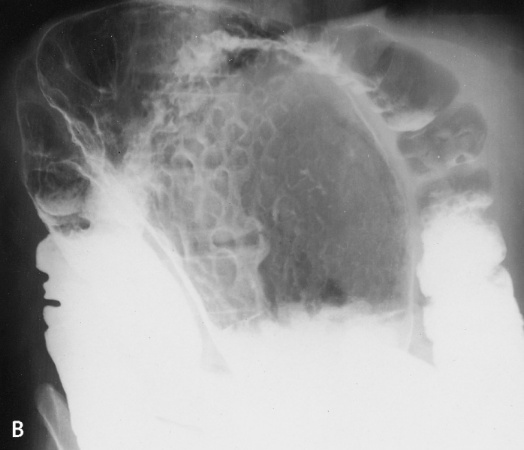

What is hyperplastic cholycystosis?

What are 2 subtypes?

Benign tissue proliferation affecting the gallbladder.

Includes adenomyomatosis (mural hyperplasia of the muscular layer and epithelial mucosa with the development of mucosa-lined diverticula Rokitansky-Aschoff sinuses) and cholesterolosis (cholesterol and triglyceride deposits in the lamina propria, aka strawberry gb).

Imaging findings in adenomyomatosis?

Differential?

Can be focal (usually in the fundus), segmental (usually in body), or diffuse.

Enhancing mural thickening plus: US: immobile, echogenic Rokitansky-Aschoff sinuses, with comet tail reverberation artifact if cholesterol crystals are present (specific).

CT: RAs are low density, surrounded by enhancing mucosa. MRI: non enhancing RAs with low T1 high T2.

Differential is gallbladder adenocarcinoma, mets (melanoma most common), polyp.